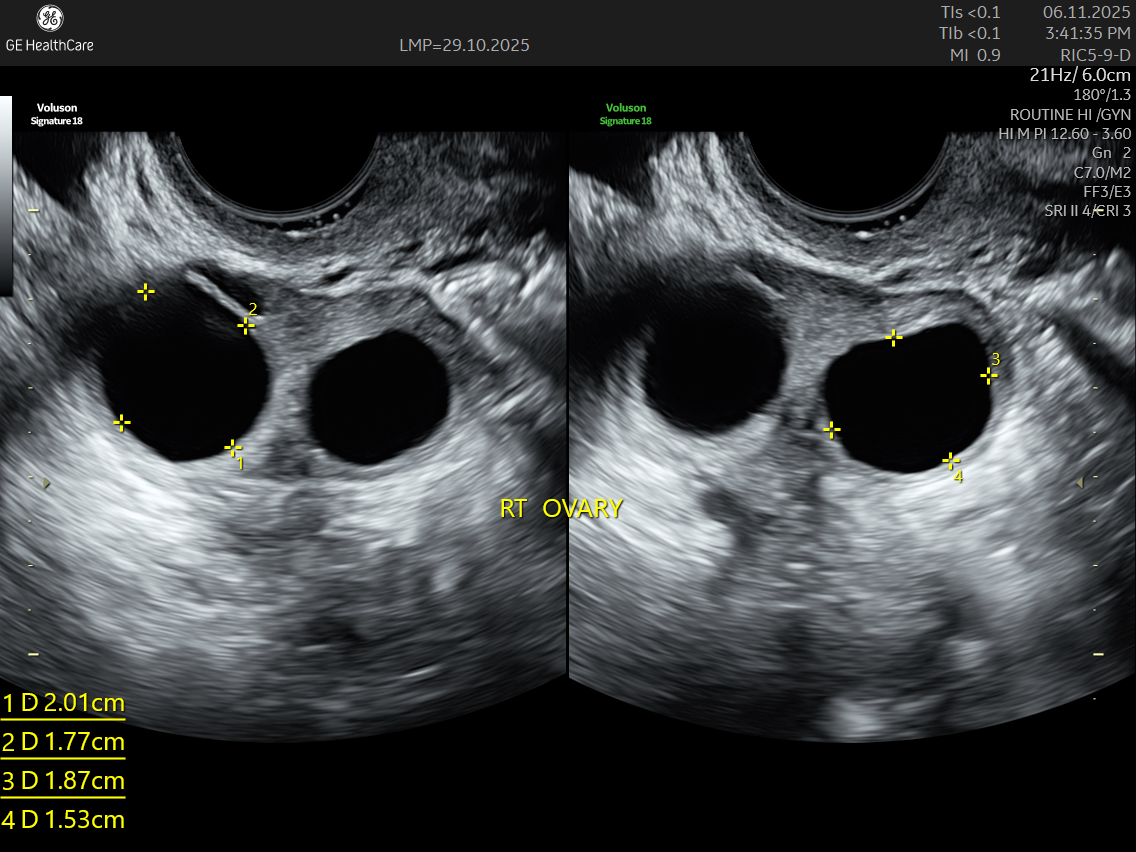

IMAGE GALLERY